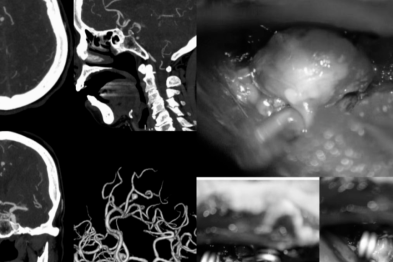

七旬高危患者命悬一线!桂医大二附院救治脑动脉瘤破裂合并重症心衰老人

2026-04-22 -